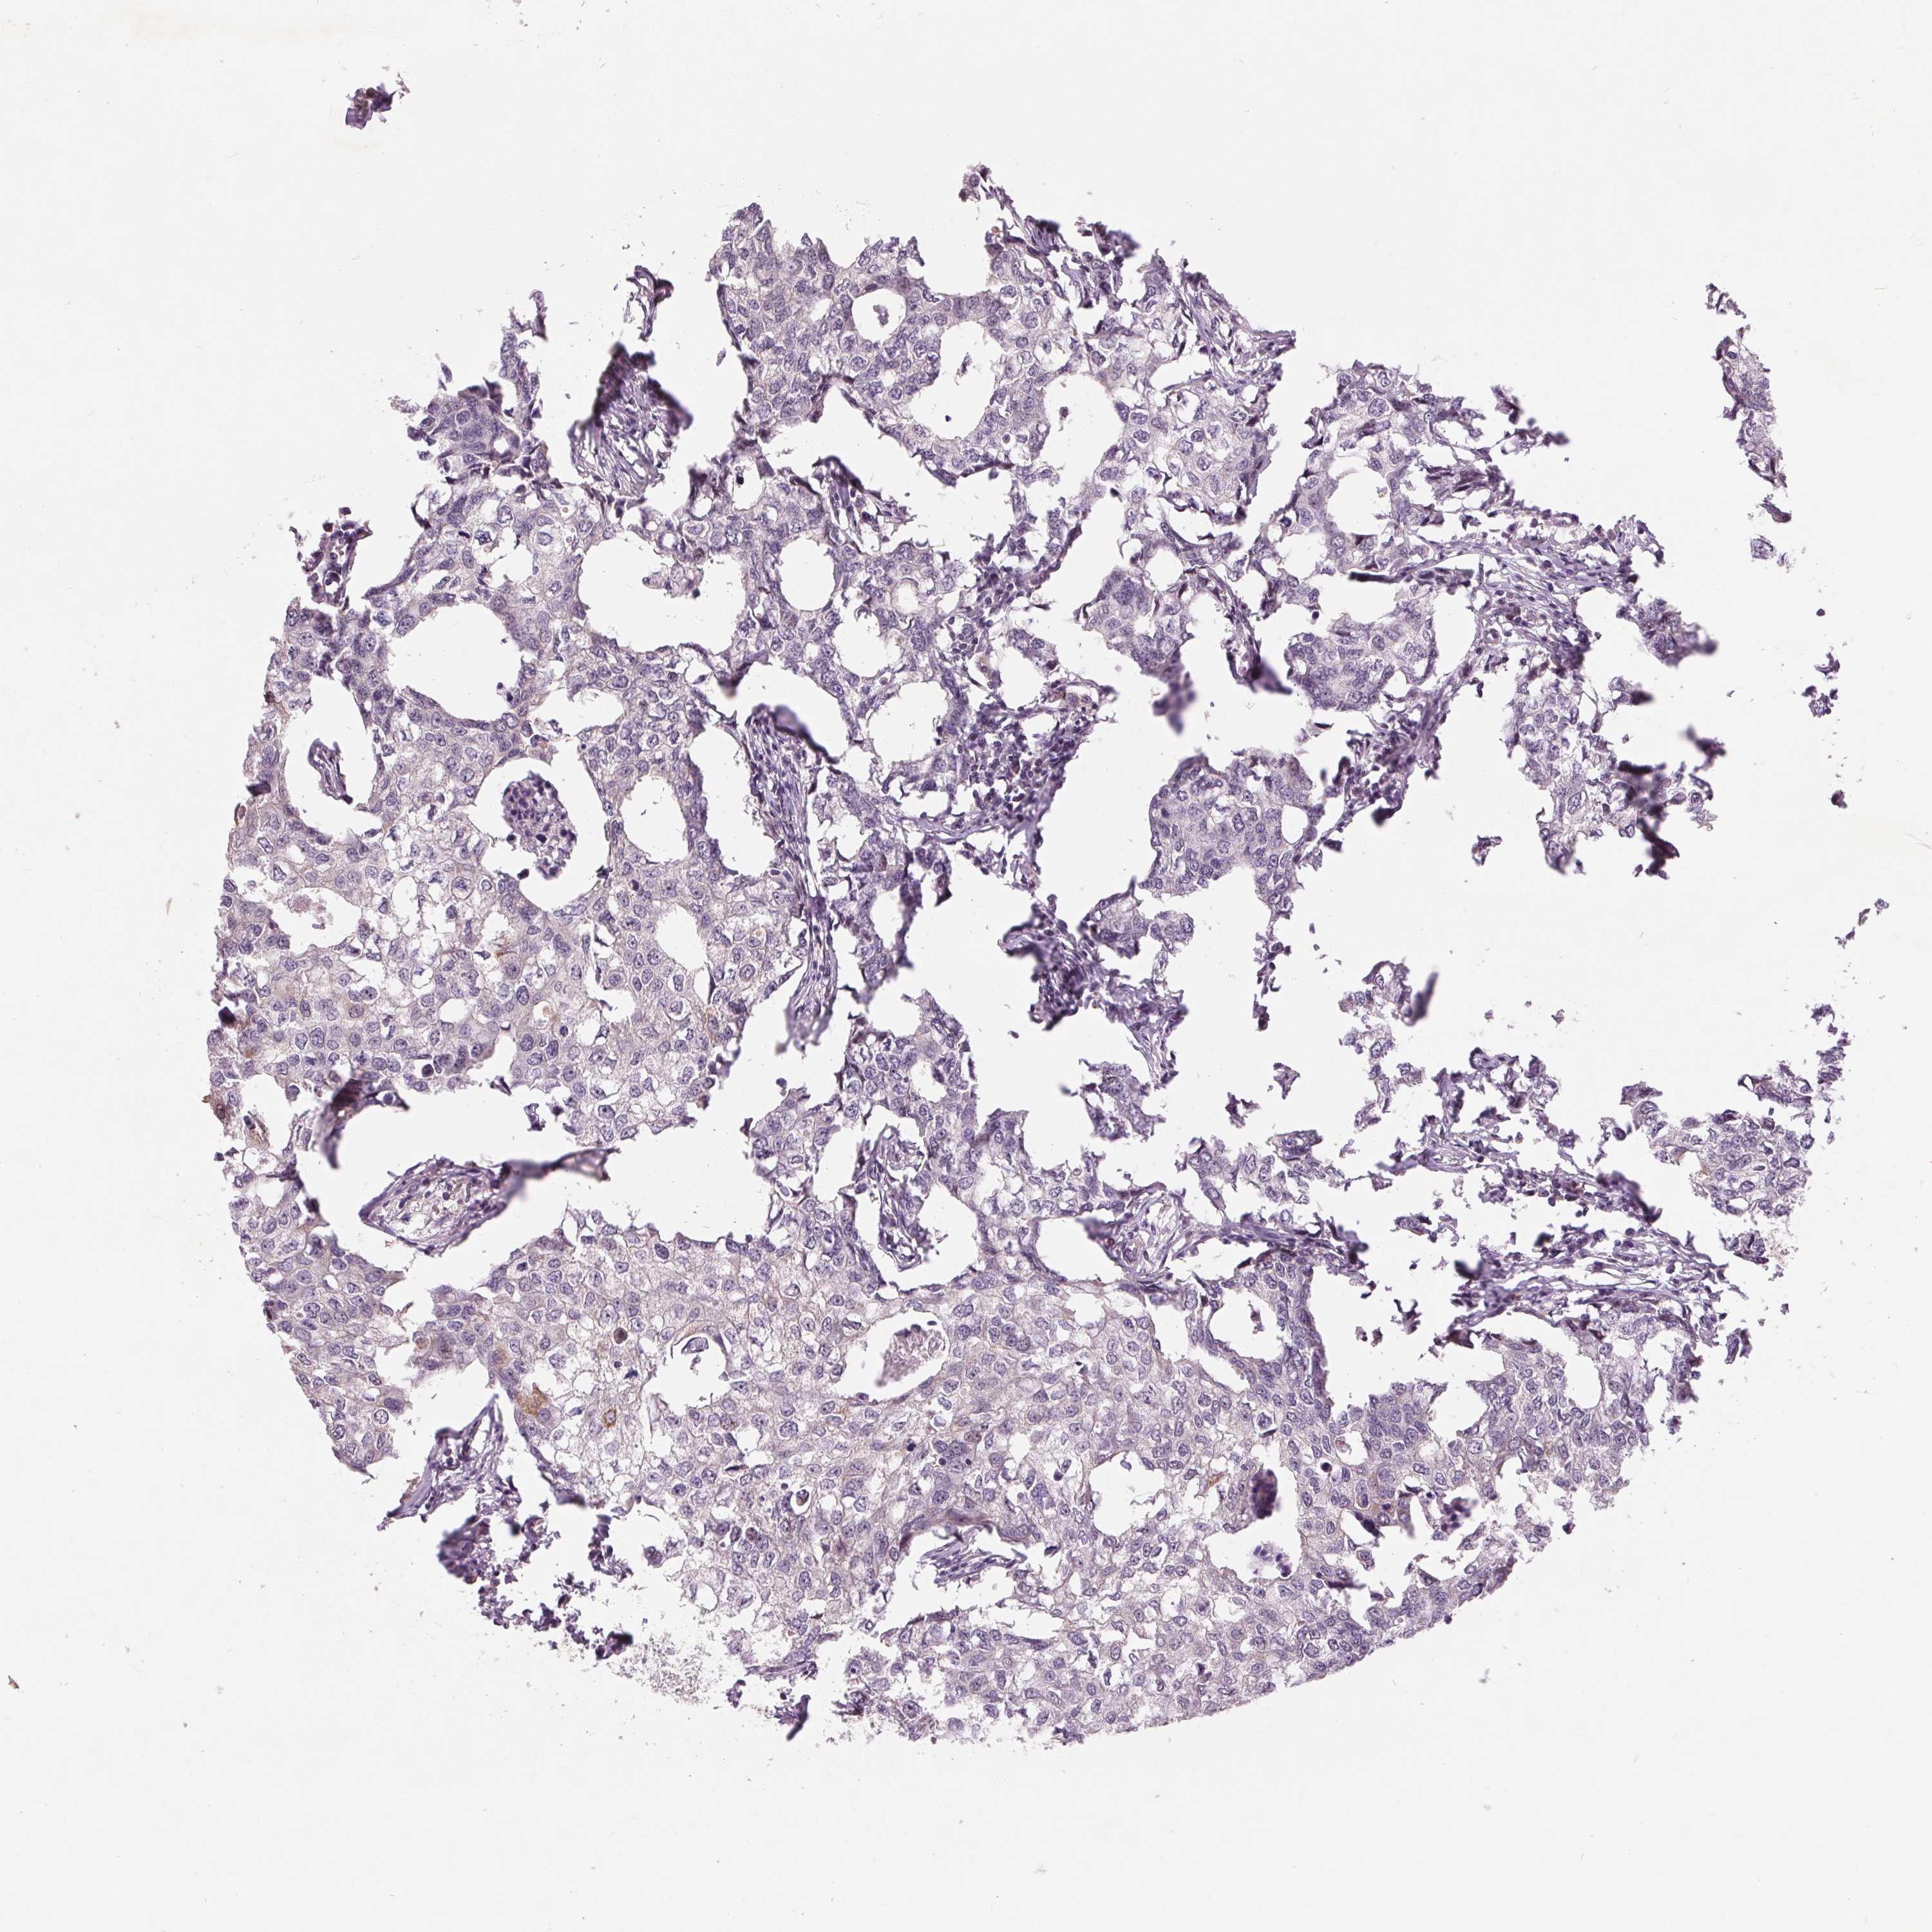

BRCA TCGA BRCA VALIDATION PROTEIN EXPRESSION

Breast cancer

Human cancer

Breast invasive carcinoma